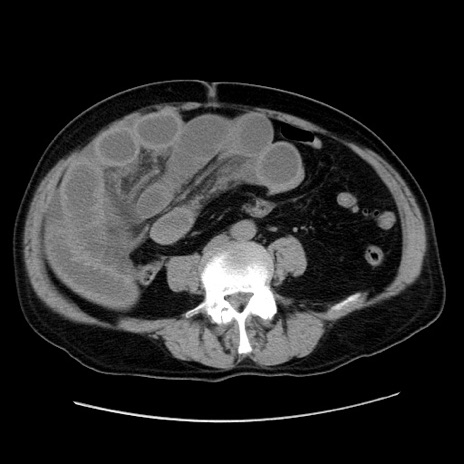

症例30(横断像)

冠状断像

【症例】80歳代男性

【現病歴】約6時間前から臍下部痛が出現。次第に腹部膨隆・背部痛も生じてきたため来院。背部痛の場所は変化しない。

【身体所見】意識清明、BT 36.3℃、BP  131/87mmHg、P 87bpm、SpO2 100%(RA)、臍周囲自発痛・圧痛あり、反跳痛なし、自発痛部位に一致して板状硬あり、腹部膨隆、腸雑音減弱、CVA tenderness両側陰性。

【データ】WBC 19600、CRP 0.33